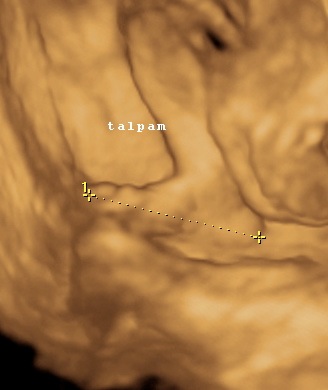

A 3D-s babafotok meg mindig lenyugoznek, nem birok betelni veluk. SZomoruan olvasom, hogy mennyi aprobb-nagyobb kellemetlensegetek van, de szerintem mindenki nagyon szuperul halad, ugyesek vagytok...le a kalappal foleg a dolgozok, vagy mar babasok elott! majd most teszek fel kepeket es is Azzurrarol, bar mar tobb, mint 5 hete keszultek, de ujabbak mar nem lesznek, es mivel kimaradtam abban az idoszakban, most potolom. Az tuti, hogy ezentul mindenkinek javasolni fogom a 4D-t ilyen koran is (22+1 hetesen voltunk), mert bar csimota ducibb volt az atlagnal es mar akkor volt rajta jo adagnyi izom (ez is a napi 1 l tej

), de egy sovanyabb baba is csodaszep szerintem...mindent el lehet mondani, csak azt nem, hogy csontkollekciok lennenek. Osszessegeben ugy nez ki, hogy ram hasonlit, de a szemoldokcsontja es a szaja az egy az egyben a parome...szerencsere...neki az sokkal szebb...remelem, haj-ugyben is ra ut majd